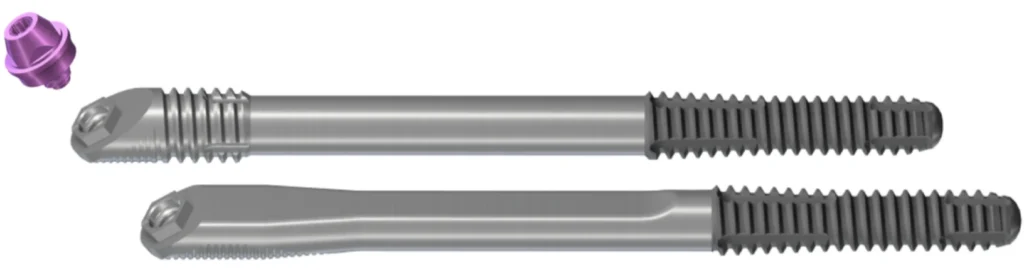

Un implant zygomatique est plus long qu’un implant en titane classique. Il mesure de 3 à 5 cm. L’os des pommettes est d’excellente qualité, il ne se résorbe pas. Son volume osseux est généralement suffisant. Chaque pommette peut recevoir un ou deux implants. La partie de l’implant visée dans l’os zygomatique est rugueuse pour une meilleure accroche et cicatrisation osseuse, l’autre partie qui traverse le sinus et la muqueuse buccale est lisse pour éviter de fixer les bactéries. Le col de l’implant est angulé à 55 degrés pour rattraper l’axe d’insertion. Un pilier (violet) est vissé dans l’implant. Son épaisseur varie de 1 à 3 mm. Il est choisie en fonction de l’épaisseur de gencive. La prothèse se visse sur le pilier.

Il existe 2 types d’implants zygomatiques, un avec un col fileté pour augmenter son accroche si le volume osseux le permet au niveau du maxillaire et un avec un col plat affleurant pour épouser les contours osseux si le maxillaire est atrophié. Si le col de l’implant est en sur-épaisseur sur le rebord osseux et non complètement entouré d’os, il y a un risque important de rétraction muqueuse et d’exposition de l’implant à l’origine d’une possible porte d’entrée bactérienne et d’une gène pour le patient.